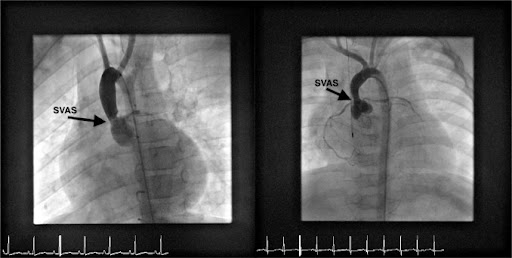

Widespread arteriopathy secondary to an elastin gene defect results in various cardiac defects including supravalvar aortic stenosis SVAS and coronary artery. Williams syndrome affects approximately one in 10 000 people and is caused by the deletion of genes on chromosome 7q1123 which code for elastin. Williams Syndrome and Anesthesia in a Large Unselected Cohort. Fixed cardiac output and myocardial ischemia leading to dyspnea and angina. A 4 year old boy with Williams syndrome developed masseter spasm after halothane and suxamethonium. The surgery was accomplished with a nontriggering anaesthetic and no further problem. All William syndrome patients undergoing non-cardiac surgical interventional or imaging studies are cared for by main operating room pediatric anesthesiologists. Williams syndrome WS also known as Williams-Beuren syndrome is caused by a deletion of part of chromosome 7 and is a multisystem disorder that was first identified as a distinct clinical entity in 1961. The phenotypic appearance of people with Williams syndrome is well characterized but there continues to be new genetic and therapeutic discoveries.